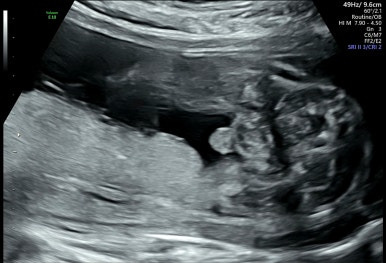

9주 1일차

젤리곰 같은 태아를 볼 수 있다! 벌써 손발이 생겨 움직이는 모습이 너무 신기하다.

이 시기는 평소보다 심장이 원래 빨리 뛰는 시기이다.